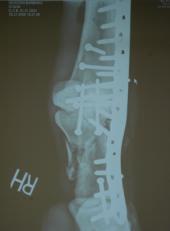

So far so good this morning for Barbaro! Fingers crossed that he survives and lives the happy life of a stud. Susan That last shot is Barbaro AFTER surgery!

Richardson worked with six other doctors in a surgery requiring a metal rod and 23 screws to stabilize several bones that had shattered into more than 20 pieces. The surgeon says the horse is comfortable but must still avoid infection, circulation problems and other dangers during his recovery.